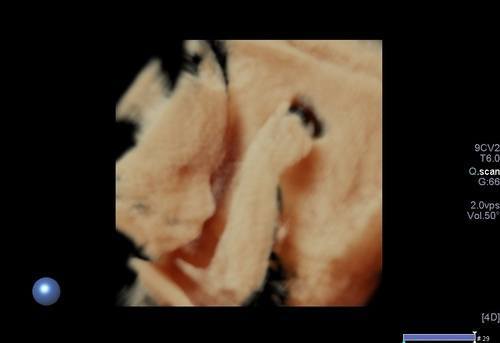

3/4 boyutlu ya da renkli ultrason olarak adlandırılan inceleme ise bebeğin yüzü ya da vücudunun bir kısmının (kollar, bacaklar, eller,ayaklar gibi ) görüntülenmesi anlamına gelir. Bu incelemenin tanısal bir katkısı olmamakta olup daha çok anne, baba ve yakınları için hatıra için yapılmaktadır.